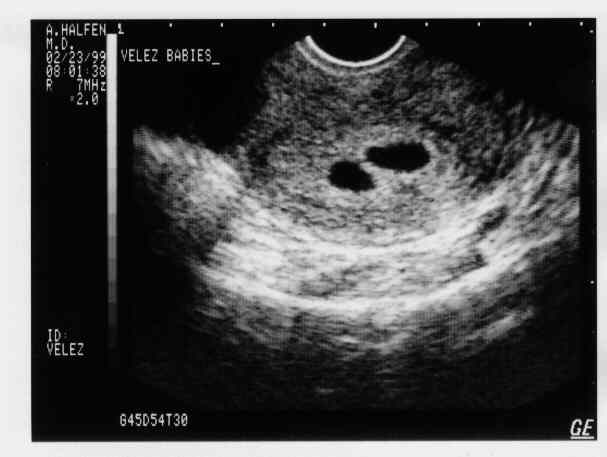

eggs2.JPG - 19.8 K eggs3.JPG - 22.4 K eggs4.JPG - 11.7 K babies-1a.JPG - 21.3 K